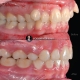

درمان ارتودنسی بدون کشیدن دندان در کیس با نیش های بیرون زده در مدت ۲۰ ماه انجام شد. دیستالیزیشن فک بالا با استفاده از Tad system جهت کسب فضای مورد نیاز برای دندانهای نیش بیرون زده انجام شد.

Non extraction orthodontic treatment of blocked canine on both sides done within 20 months. Distalization of upper arch using Tad system done in order to achieve required space for blocked canine.